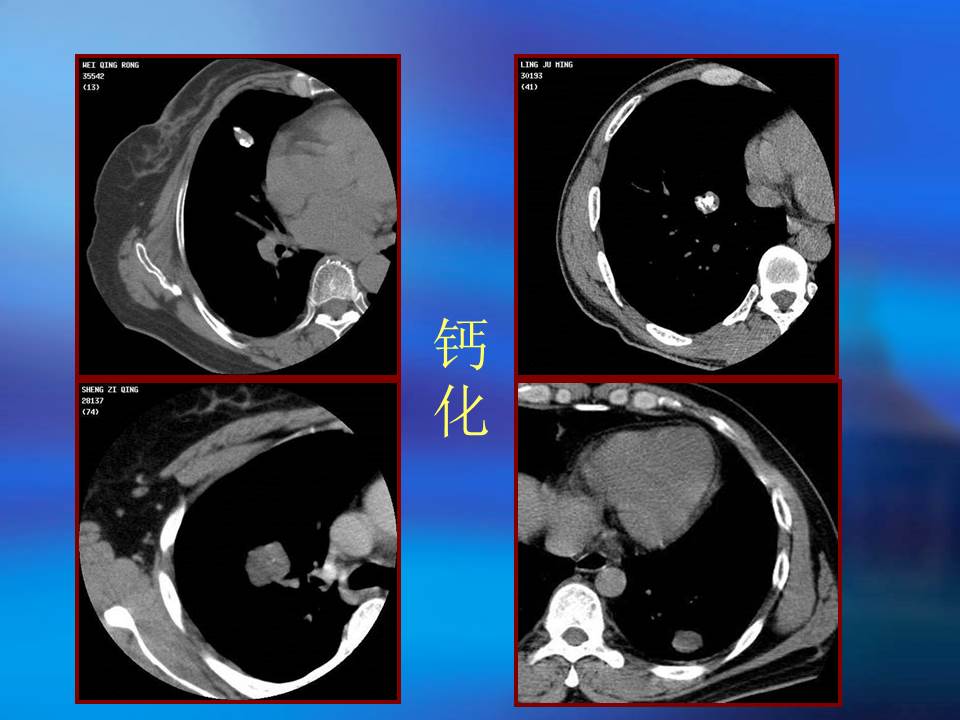

幻灯片2